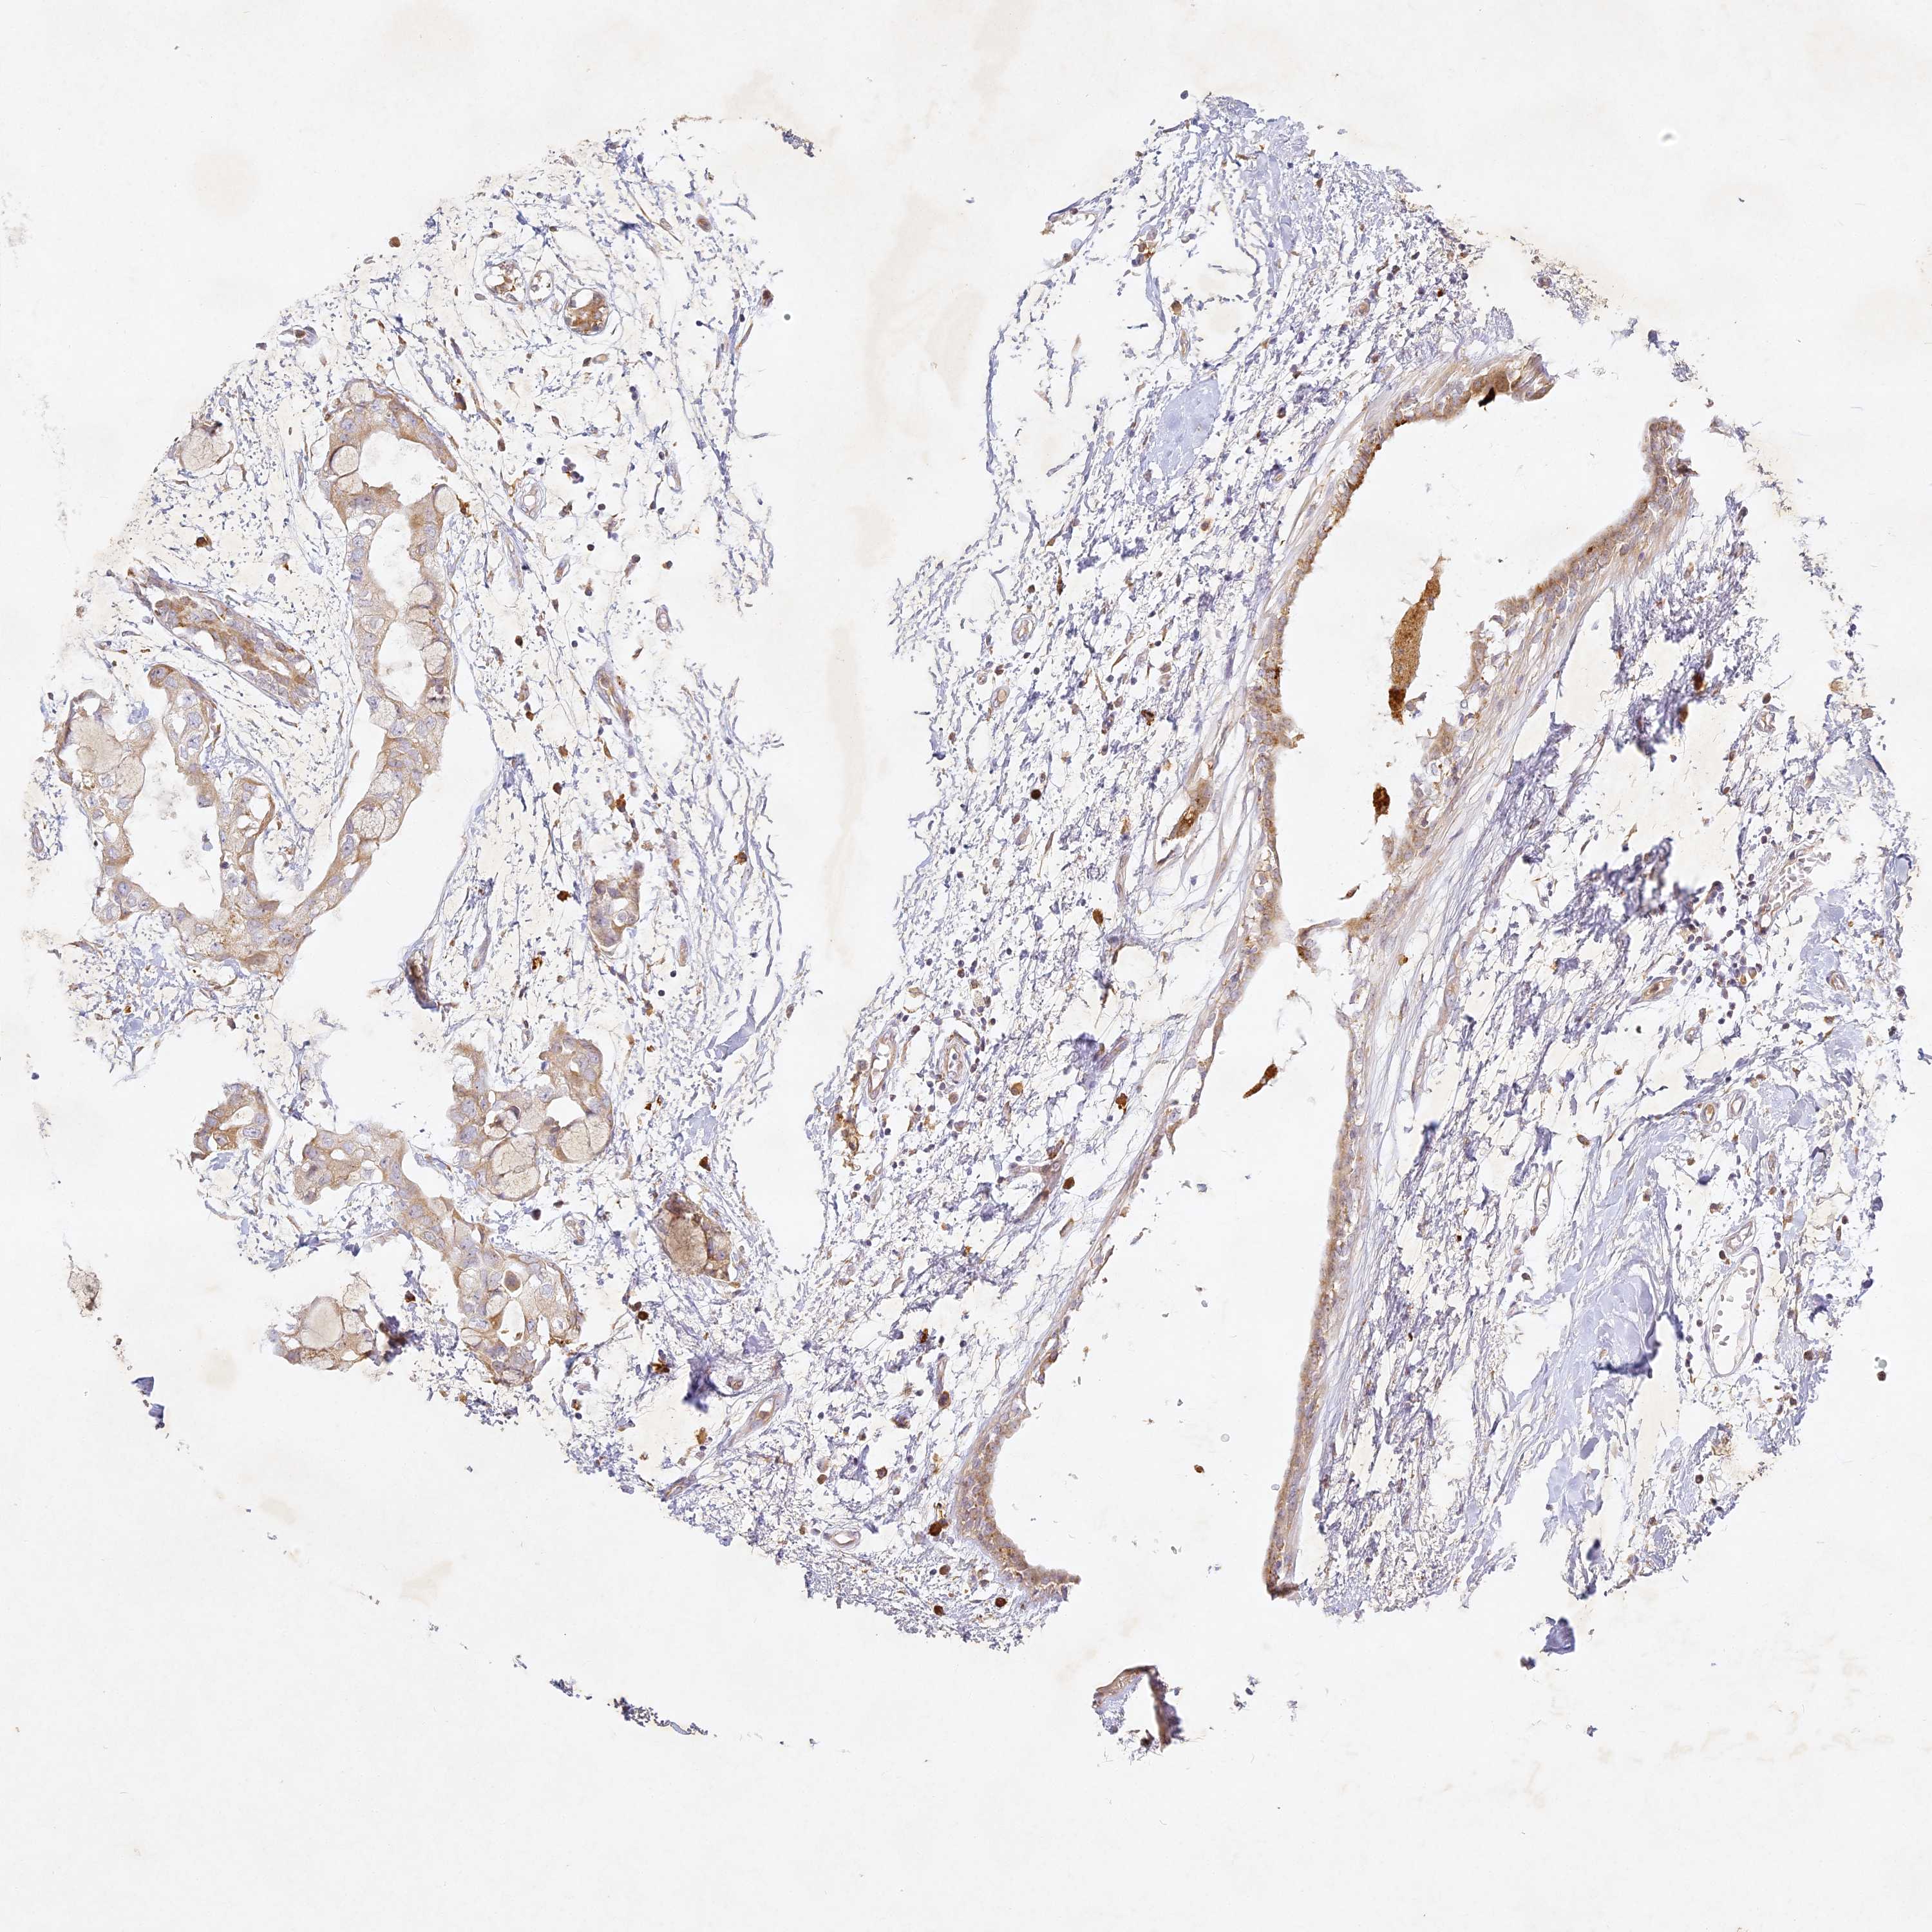

CANCER BREAST CANCER Show tissue menu

BRCA TCGA BRCA VALIDATION PROTEIN EXPRESSION